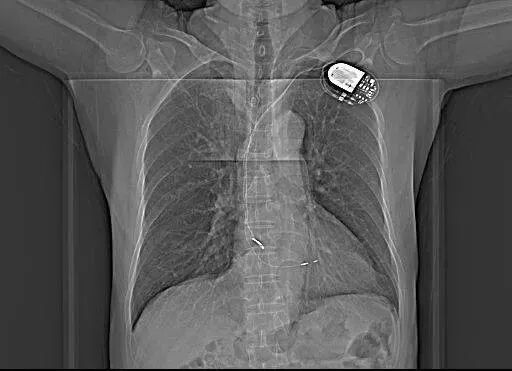

患者是双腔起搏器,DDD起搏模式。

1.DDD起搏器,心房感知和起搏、心室感知和起搏的DDD起搏方式,呈房室顺序起搏。